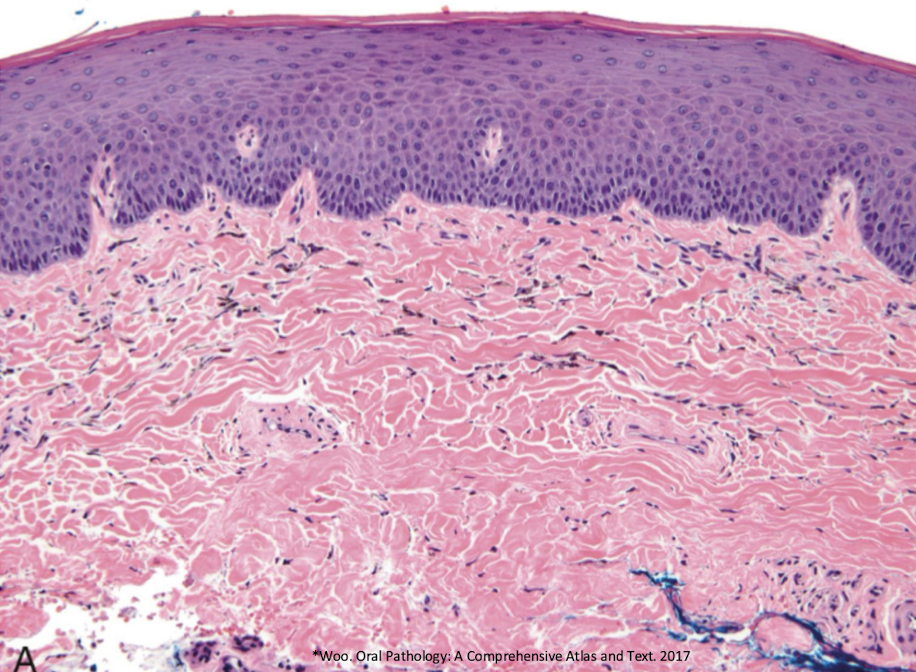

which pigmented lesion

amalgam tattoo

amalgam tattoo,

L: purple epithelial lining and the pink the middle is the scar you can see through epithelium (graphite won’t do this)

which pigmented lesion histopathological features?

pigmented fragments

staining of reticulin fibers

large fragments surrounded by fibrosis

amalgam tattoo (exogenous, non-melanated)